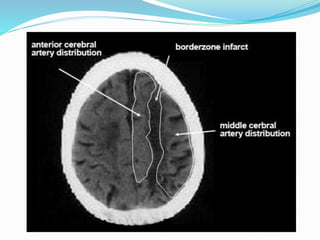

• Two basic patterns: “border zone infarcts” and

“generalized cortical necrosis.

Hypoxic-Ischemic Injury

• The most frequently and severely affected area is the

parietooccipital region at the confluence between the ACA,

MCA, and PCA territories.

• Most common observed on NECT is a low density band at

the interface between major vascular territories.